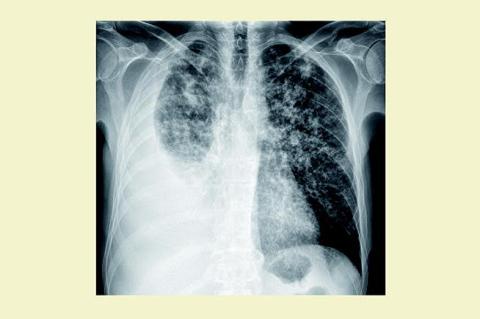

En 49-årig mand med svær morbus Bekhterev (aksial og perifer artritis) diagnosticeret i 2004 blev behandlet med tumornekrosefaktor (TNF)-a-inhibitoren infliximab 500 mg givet intravenøst hver sjette uge samt tablet methotrexat 20 mg ugentligt. Patienten henvendte sig til den 23. infliximab-infusion med klager over åndenød, tør hoste, træthed og vægttab. Han var akut medtaget og hviledyspnøisk med perifer O2-saturation 87%. Stetoskopisk blev der fundet svækket respirationslyd på højre lungefelt. Patientens antireumatiske behandling blev seponeret. Røntgen af thorax viste diffuse nodulære fortætninger i begge lungefelter og højresidig pleuraansamling. Mikroskopi af pleuravæsken viste ingen syrefaste stave, men polymerasekædereaktionsdiagnostik var positiv for Mycobacterium tuberculosis. Endvidere var der positiv plasma-gamma-interferon. Før behandlingsstart med infliximab var der negativt resultat af en Mantouxtest og normale forhold set ved røntgenfotografering af thorax. Patienten kendte ikke sin tuberkulosevaccinationsstatus.

TNF-a-hæmmere anvendes til behandling af aktiv reumatoid artritis, morbus Bekhterev og morbus Crohn. Grundet den immunsupprimerende virkning af behandlingen er jævnlig ambulant kontrol nødvendig. Negativ screening for tuberkulose inden behandlingsstart udelukker ikke med sikkerhed latent tuberkulose, patienter, som får tegn på infektion, må derfor udredes grundigt.